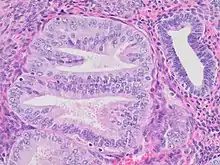

- Architectural gland crowding

- Altered cytology relative to background glands

- Minimum size of 1 mm

- Exclusion of adenocarcinoma

- Exclusion of mimics

Mitoses should also preferably be seen. Compare to normal endometrial gland at right.

EIN may be diagnosed by a trained pathologist by examination of tissue sections of the endometrium. All of the following diagnostic criteria must be met in a single area of one tissue fragment to make the diagnosis (Table III).

| 1 | Architecture | Gland area exceeds that of stroma, usually in a localized region. |

| 2 | Cytological Alterations | Cytology differs between architecturally crowded focus and background. |

| 3 | Size greater than 1mm | Minimum linear dimension should exceed 1mm. Smaller lesions have unknown natural history. |

| 4 | Exclude mimics | Basalis, normal secretory, polyps, repair, lower uterine segment, cystic atrophy, tangential sections, menstrual collapse, disruption artifact, etc. |

| 5 | Exclude Cancer | Carcinoma should be diagnosed if: glands are mazelike and rambling, there are solid areas of epithelial growth, or there are significant bridges or cribriform areas. |